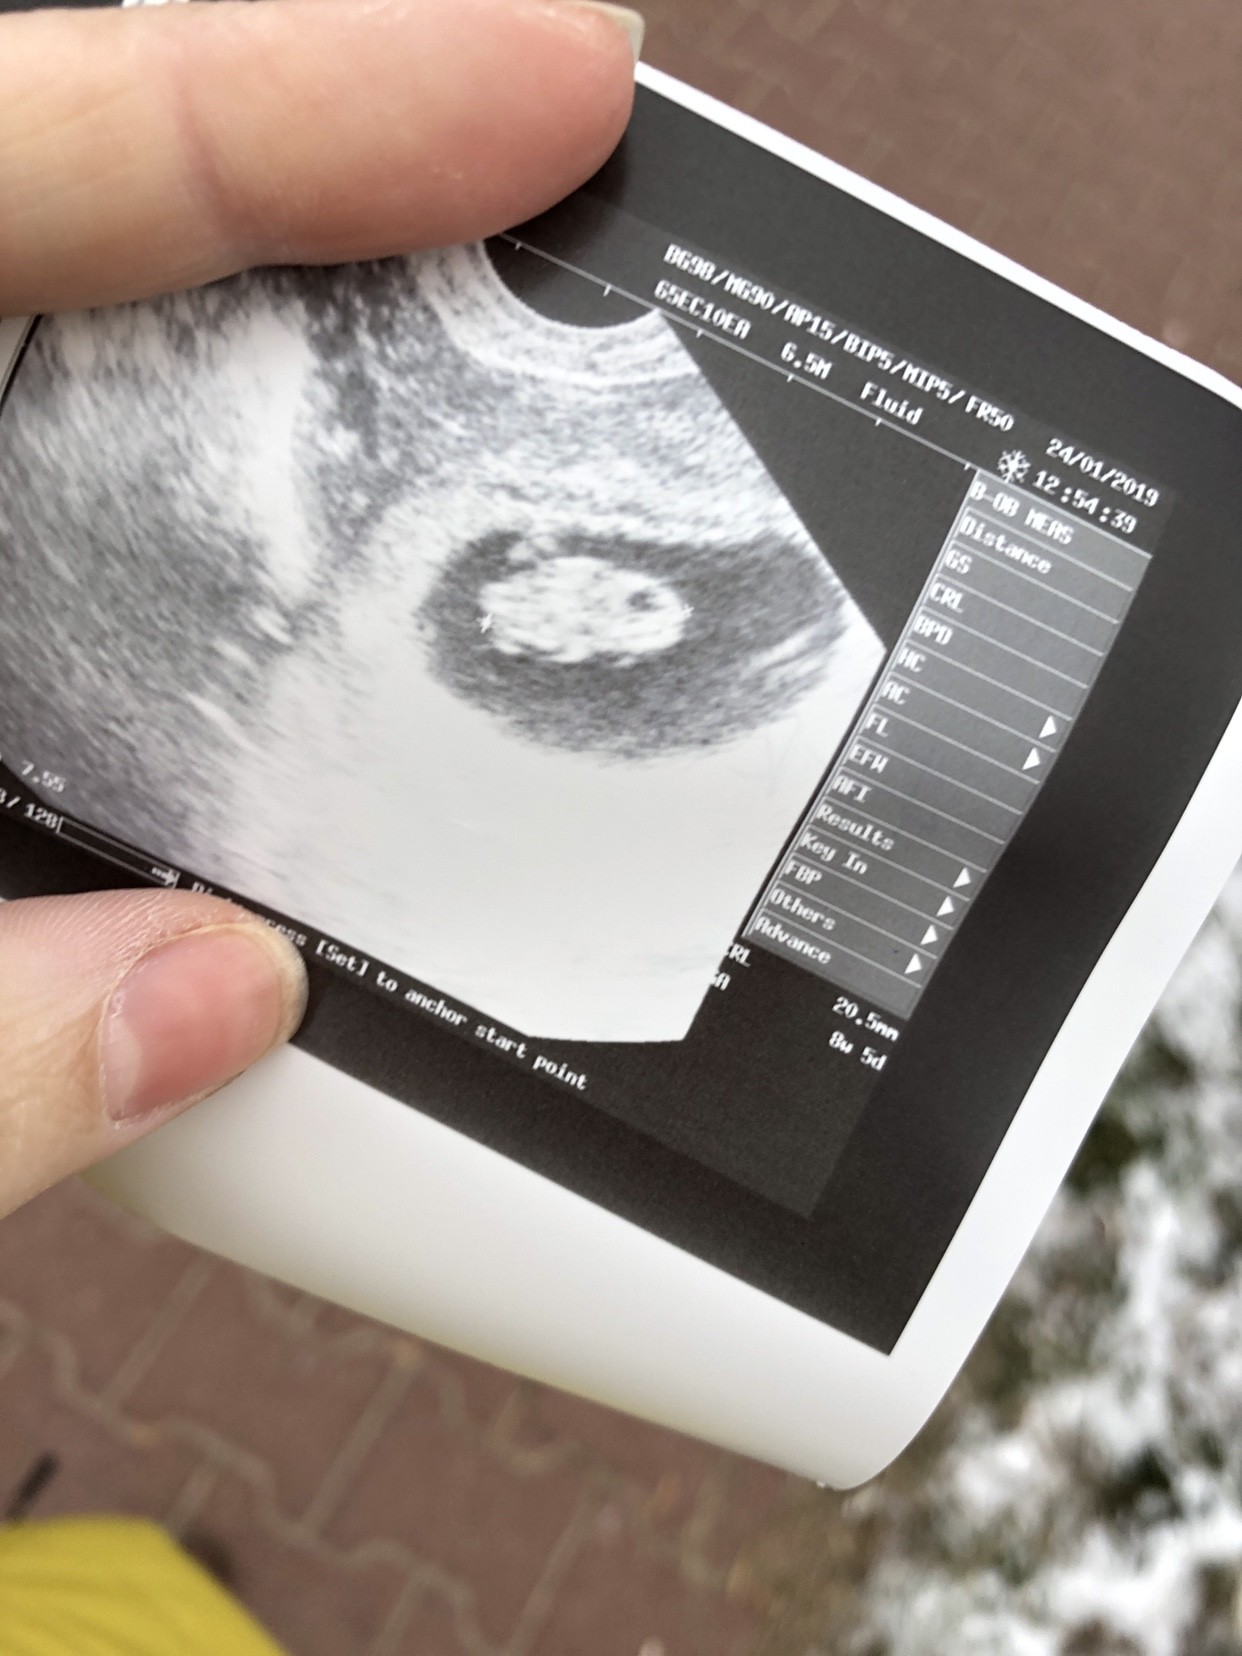

Super!!! To nasze maleństwa mają podobny wymiar hehe...najważniejsze że wszystko okZobacz załącznik 936468

Oto moje 2cm człowieka [emoji173]️

Z usg wyszło dziś 8+5tc

Serduszko jak dzwon. Umawiać sie na prenatalne.

moje 2cm człowieka [emoji173]️